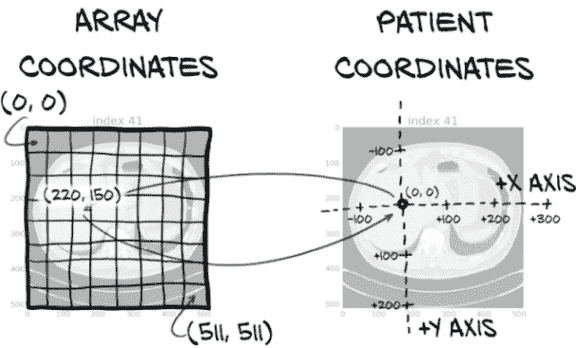

10.4.1 患者坐标系

不幸的是,我们在第 10.2 节加载的所有候选中心数据都是以毫米为单位表示的,而不是体素!我们不能简单地将毫米位置插入数组索引中,然后期望一切按我们想要的方式进行。正如我们在图 10.5 中所看到的,我们需要将我们的坐标从以毫米表示的坐标系(X,Y,Z)转换为用于从 CT 扫描数据中获取数组切片的基于体素地址的坐标系(I,R,C)。这是一个重要的例子,说明了一致处理单位的重要性!

病人坐标系以毫米为单位测量,并且具有任意位置的原点,不与 CT 体素数组的原点对应,如图 10.7 所示。

图 10.7 数组坐标和病人坐标具有不同的原点和比例。

病人坐标系通常用于指定有趣解剖的位置,这种方式与任何特定扫描无关。定义 CT 数组与病人坐标系之间关系的元数据存储在 DICOM 文件的头部中,而该元图像格式也保留了头部中的数据。这些元数据允许我们构建从(X,Y,Z)到(I,R,C)的转换,如图 10.5 所示。原始数据包含许多其他类似的元数据字段,但由于我们现在不需要使用它们,这些不需要的字段将被忽略。